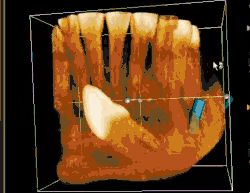

Occasionally, an impacted tooth causes sufficient pressure on the roots of adjacent teeth causing it to resorb.

An impacted tooth occupies space that is usually filled with bone. This weakens that area of bone and renders the jaw more susceptible to fracture.

When impacted teeth are retained completely within the alveolar process, the associated follicular sac is also retained along with it. Though in most persons the dental follicle maintains its original size sometimes it may undergo cystic degeneration and become a dentigerous cyst or a keratocyst.